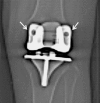

Methods: We retrospectively reviewed 57 patients undergoing primary TKAs using patient-specific custom cutting blocks for osteoarthritis and compared them with 57 matched patients undergoing TKAs with traditional instrumentation during the same period (January 2009 to September 2010). At baseline, the groups were comparable with respect to age, sex, and BMI. We collected data on operative time (total in-room time and tourniquet time) and measured component alignment on plain radiographs.

Results: On average, TKAs performed with patient-specific instrumentation had similar tourniquet times (61.0 versus 56.2 minutes) but patients were in the operating room 12.1 minutes less (137.2 versus 125.1 minutes) than those in the standard instrumentation group. We observed no difference in the femorotibial angle in the coronal plane between the two groups.